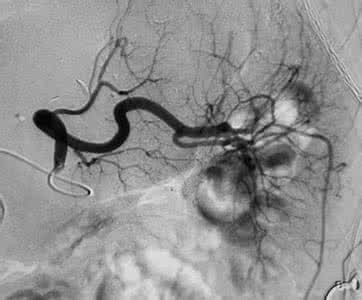

非药物治 疗包扩射频消融治疗、外科手术治疗和起搏治疗等,其适用 于药物方法治疗房颤效果不佳或不适合药物治疗的病人,成功的射频 消融治疗和外科手术治疗可以治愈房颤,虽然遗憾的是这两 种方法到目前为止成功率最高也只有90%,但令人欣慰的是近几年 成功率在不断提高。